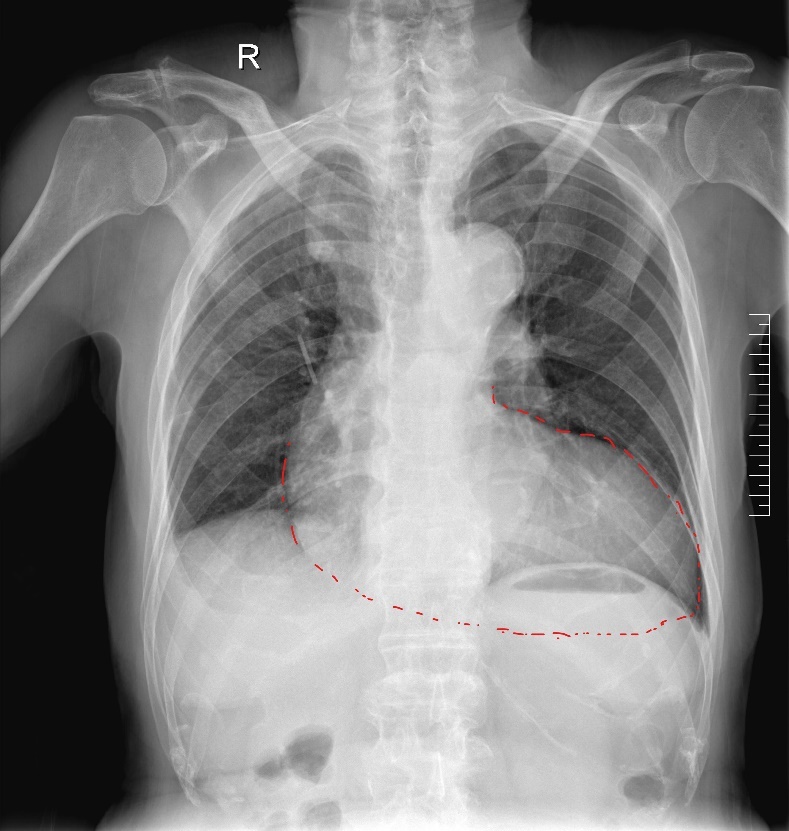

DR:极度横位心,心脏角度103°

1.功能性二叶瓣,右无冠窦融合,重度钙化,左窦小,LCA开口高度9.4mm,极度横位心,心脏角度103°;

2.患者极度横位心,升主动脉及降主动脉3D扭曲,主动脉根部几呈鱼钩样,极大增加输送系统推送及瓣膜释放难度;

1.本例患者极度横位心,心脏角度高达103°,极大增加瓣膜释放难度,瓣膜到位后,输送系统类似螺纹状,力量传导严重不同轴,提拉的力量不易把握,易导致瓣膜下滑或者弹出,同时,该患者升主动脉扩张,主动脉无贴靠,瓣膜固定主要依赖瓣环及瓣上结构。